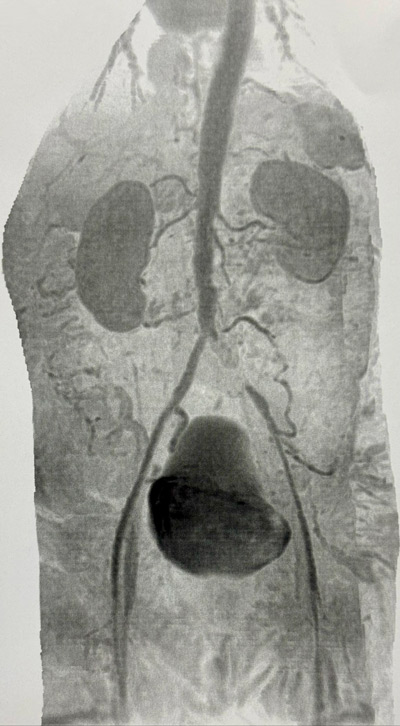

- Final angiogram: well-positioned patent stent, satisfactory remodeling, good contrast outflow